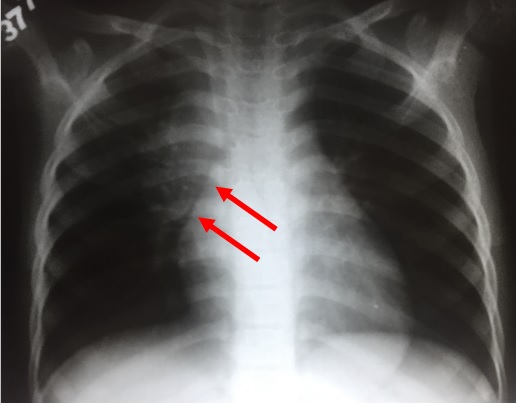

INFILTRAZIONE LEUCEMICA LINFADENOPATIA Leucemia acuta, sottotipo a cellule T radiografie del torace di un bambino di 4 anni che mostrano (a) slargamento mediastinico causato da ingrossamento timico;. A piccole cellule massa centrale con adenopatia ilare;. • segni legati alla presenza di ematoma mediastinico slargamento del profilo del mediastino.

INFILTRAZIONE LEUCEMICA LINFADENOPATIA Leucemia acuta, sottotipo a cellule T radiografie del torace di un bambino di 4 anni che mostrano (a) slargamento mediastinico causato da ingrossamento timico;. Il mediastino è un compartimento anatomico a forma di clessidra che occupa lo spazio centrale del torace compreso tra i polmoni, in cui sono contenuti il cuore, i grandi vasi ed altre strutture Tutti gli organi e strutture in esso contenuti (cuore, esofago, trachea, grossi vasi e numerosi linfonodi) possono dare luogo a patologie che prendono il nome di "mediastiniche". Mediastino translation in ItalianEnglish dictionary Showing page 1 Found 97 sentences matching phrase "mediastino"Found in 6 ms.